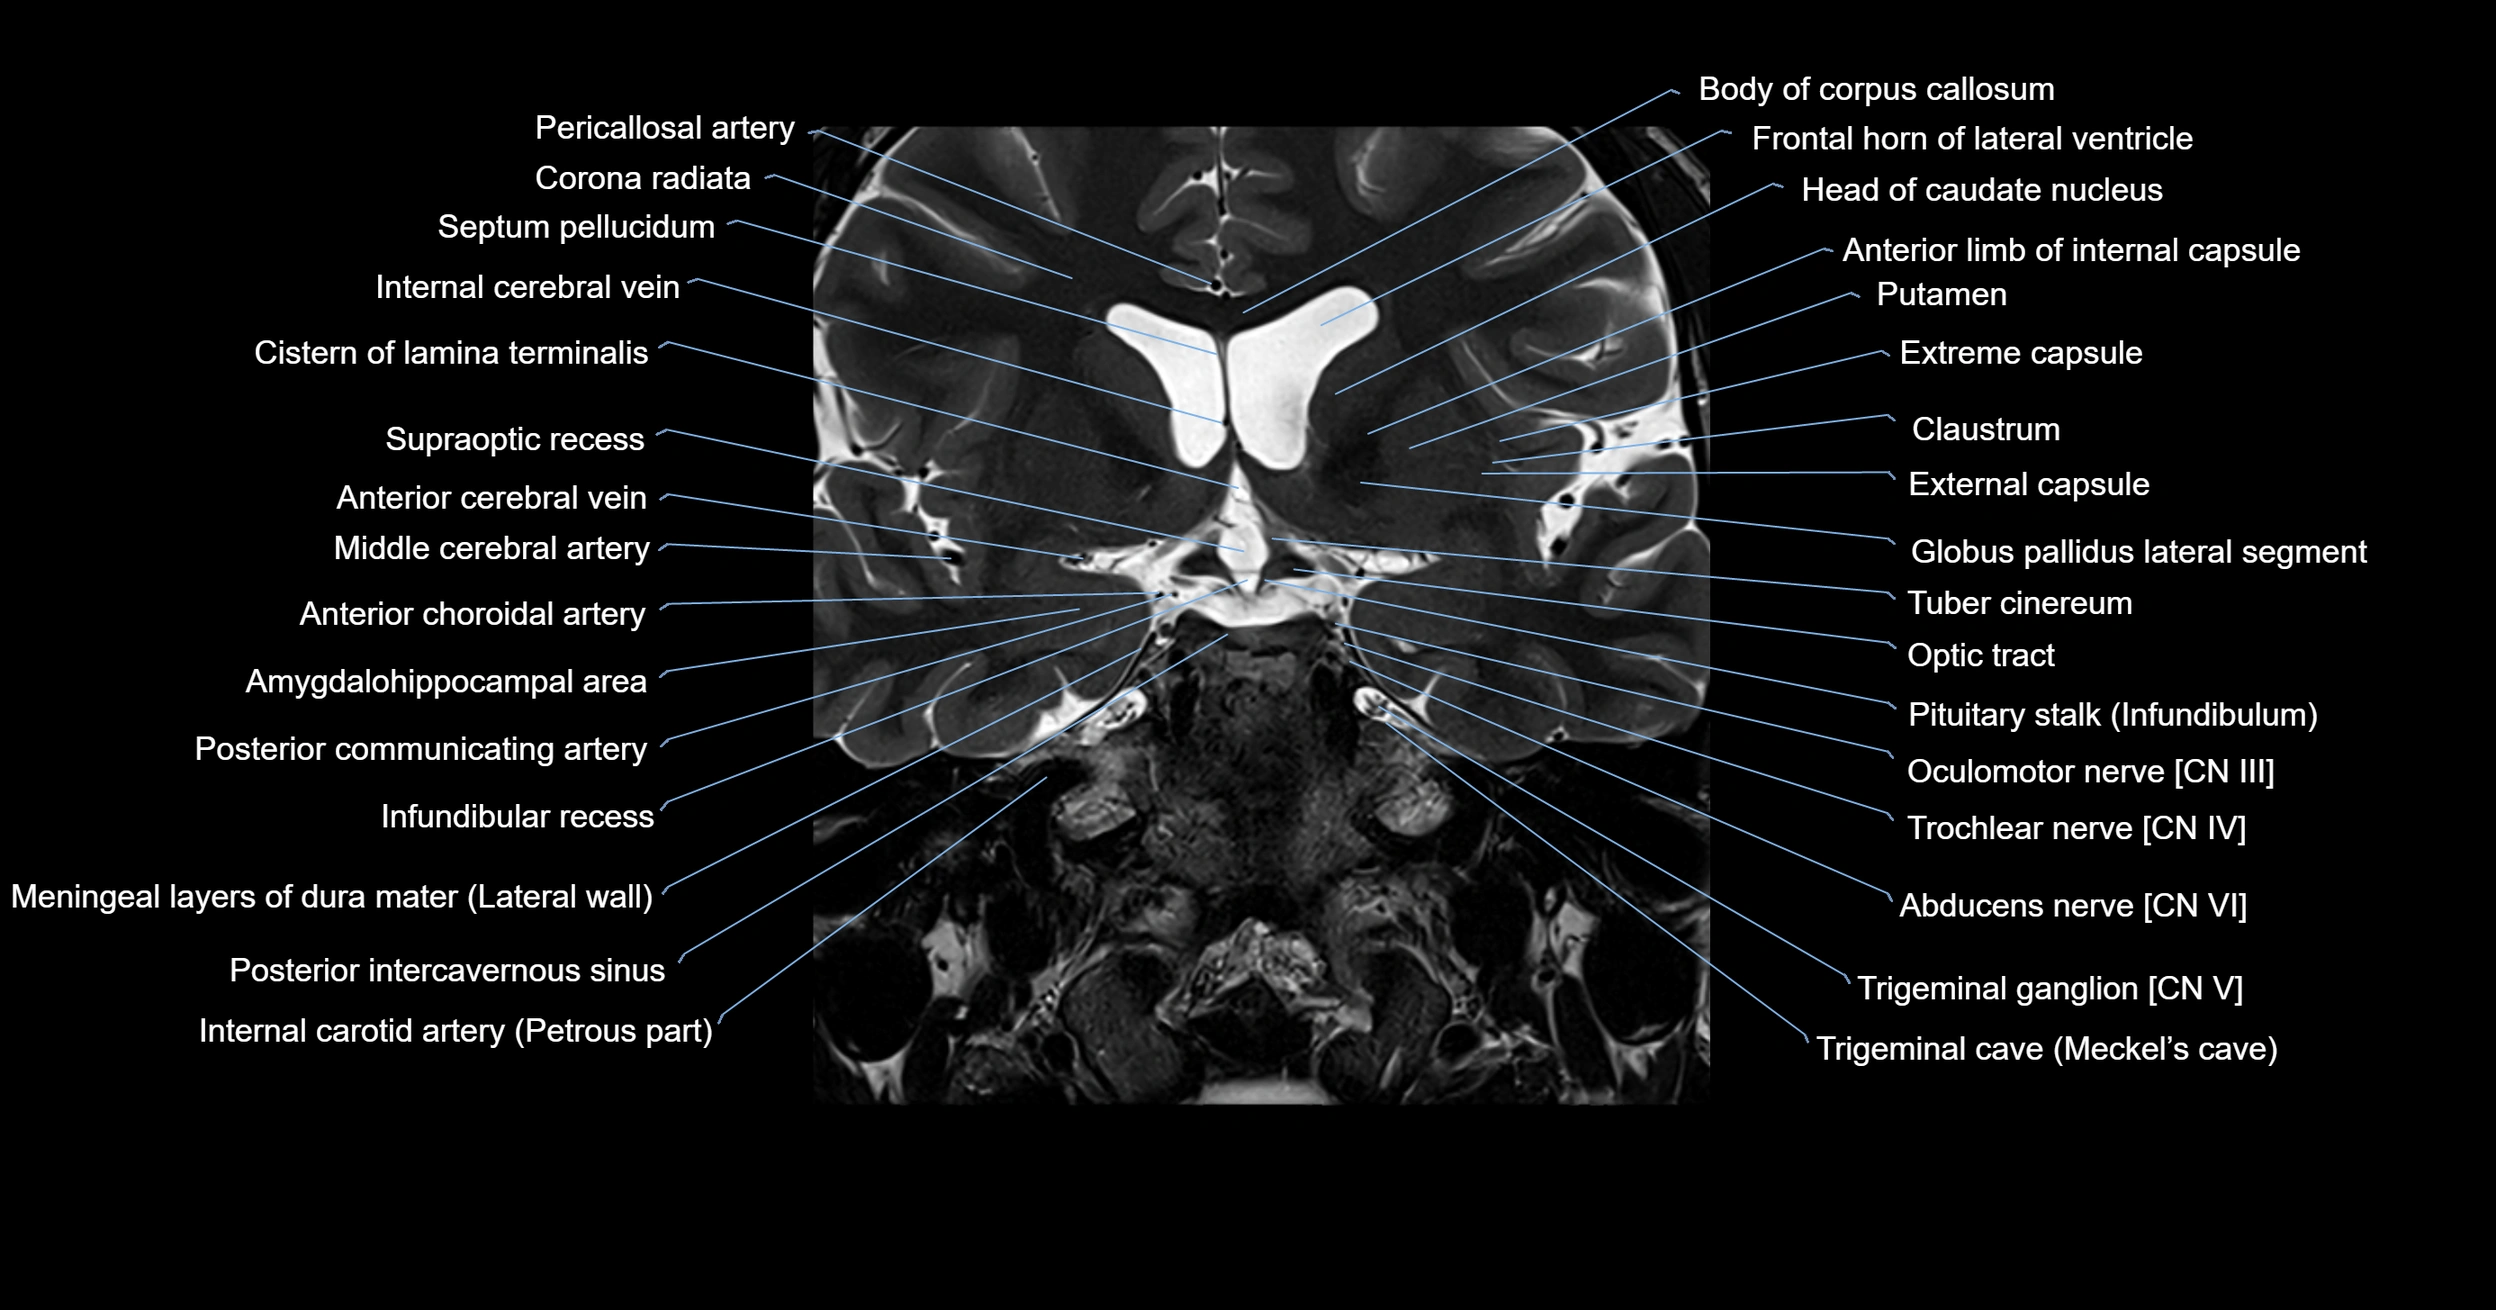

MRI images